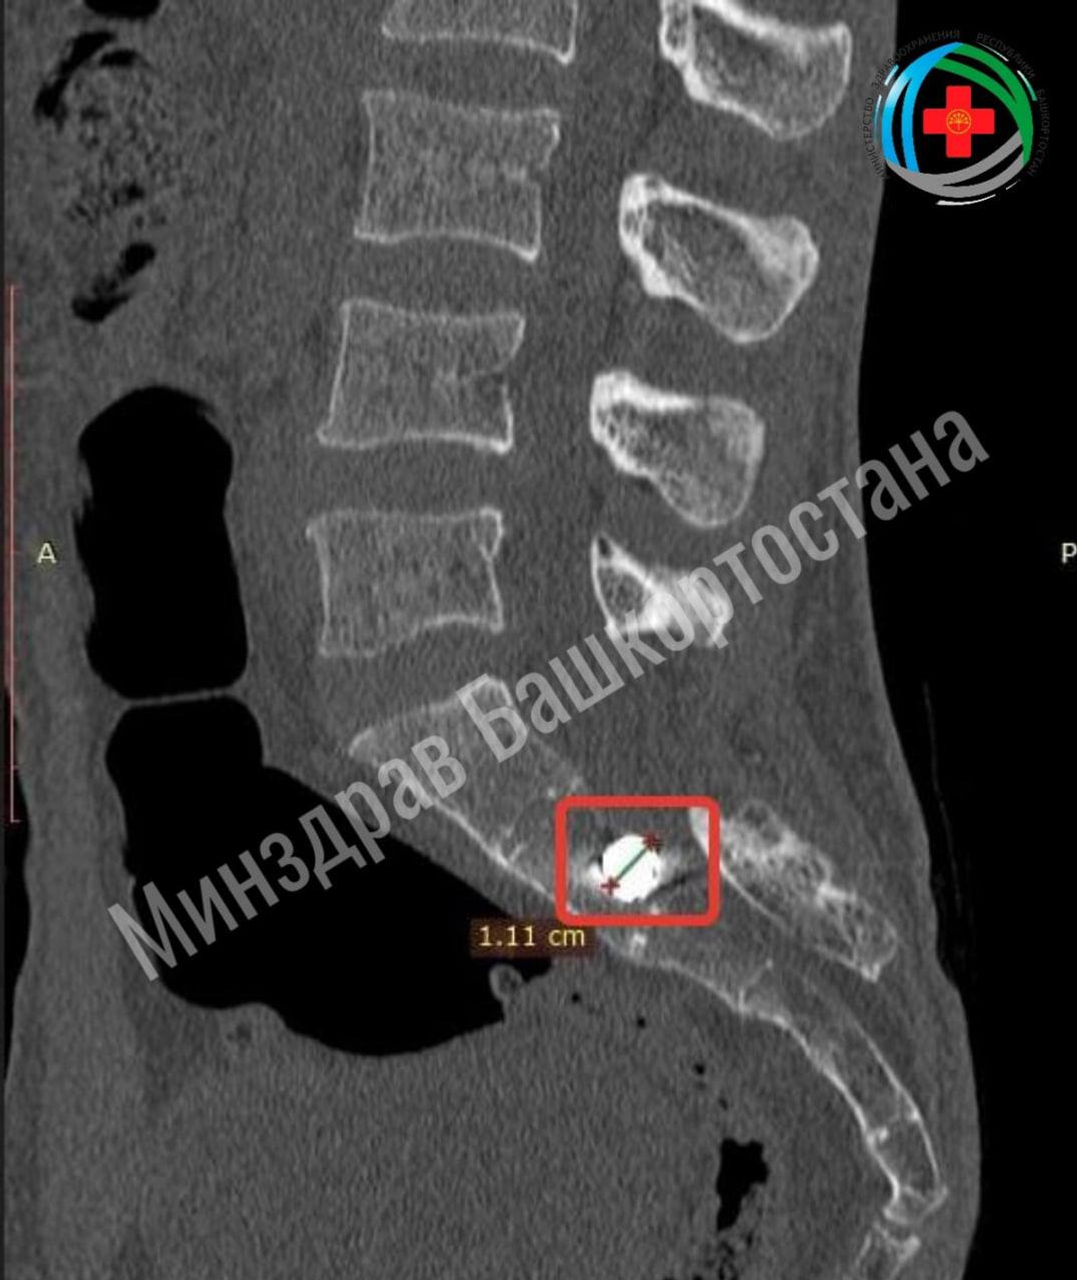

Обнаружилось осколочное ранение крестца с инородным телом, причём при отсутствии прямого раневого канала. Осколок прошёл через мягкие ткани, пробил спинной мозг и застрял в кости.

Нейрохирурги, аккуратно обойдя спинной мозг, удалили инородное тело размером 1 см.